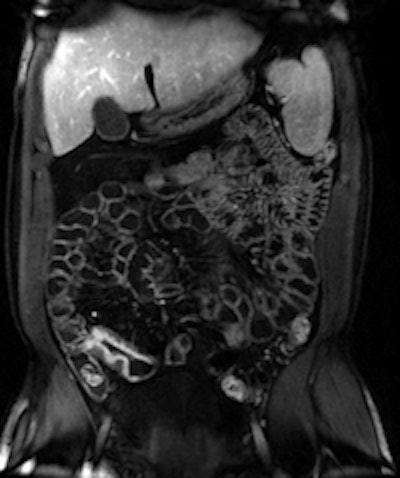

ColoVirt 2D and 3D show the same image of a small (7 mm) sessile polyp of the descending colon.Recent technical developments in radiology have improved both the detection and characterization of diseases. Advances are still ongoing, for instance with PET/CT in the management of cancer, as imaging gears up toward depicting function and metabolism, and enabling structure analysis. Striking evidence for this is the management of diffuse liver diseases, according to the ECR 2011 president.